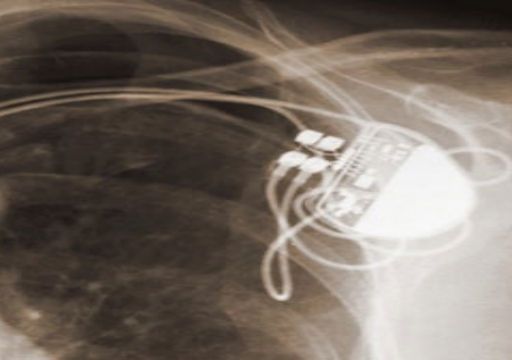

Criminal Implications of Implantable Medical Devices Since the dawn of the 1970′s television action show the Six Million Dollar Man, the public has been fascinated by bionics and the integration […]